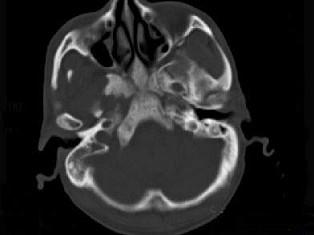

问题 男性,56岁,鼻咽癌放疗后复查,CT扫描如图所示,请选择正确的答案 ( )

选项 A、放疗后骨炎 B、骨瘤 C、骨结核 D、致密性骨炎 E、化脓性骨髓炎

答案 A